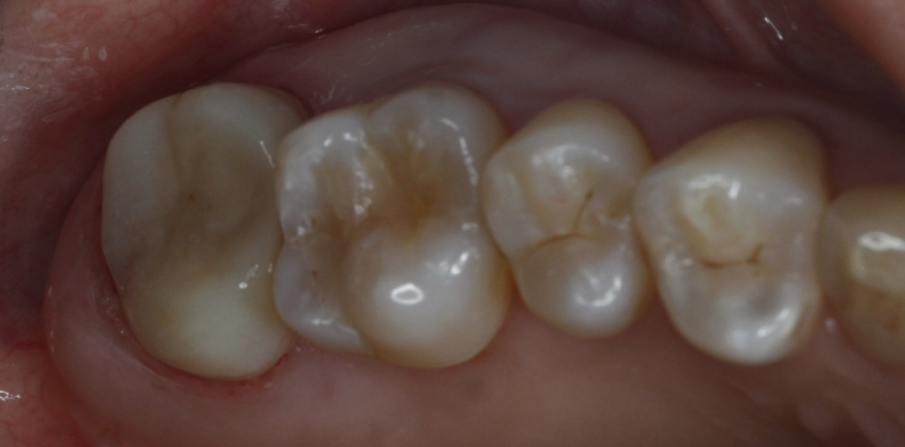

在口腔门诊中,经常碰到牙隐裂的患者就诊。牙隐裂是牙齿表面出现别的不容易被肉眼发现的细微裂纹。虽然不易被察觉,很多时候却让人觉得不舒服,有些会吃冷的东西时觉得刺激痛,有些人一咬硬东西就痛,还有人半边脸都痛…更严重的是如果裂开了,就只有拔掉了。

该患者就是因为咬硬物导致牙齿近远中横向隐裂,波及到牙髓时,牙齿受到细菌感染出现自发的疼痛症状,此时必须及早进行根管治疗来缓解疼痛。在进行彻底的根管治疗后,还需要进行冠修复来保护牙齿不再进一步裂开。